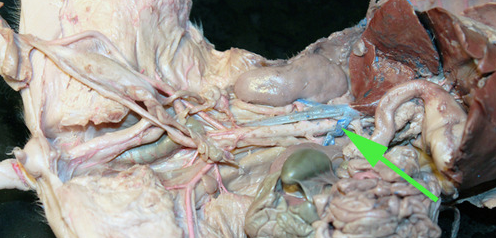

The organ marked by the green arrow arrow is the Spleen

The organ indicated by the green arrow is the SPLEEN